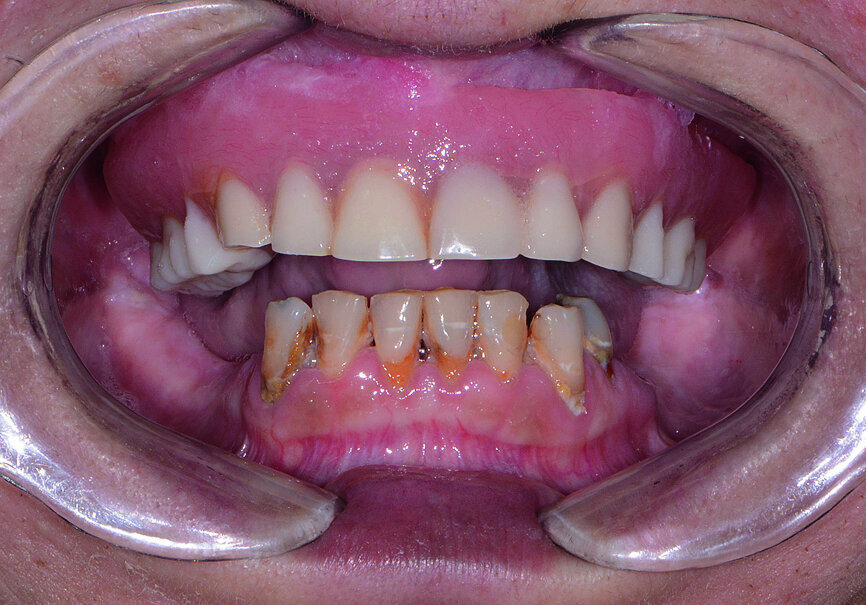

Fig. 1: Pre-op retracted view.

Fig. 2: Pre-op retracted view without denture.

A female patient in her mid-fifties presented for treatment with an edentulous maxilla and grossly decayed, hyper-erupted mandibular dentition (Figs. 1 & 2). The patient was a heavy smoker, had not seen a dentist in several years, and was not taking proper care of her remaining teeth owing to pain and discomfort. The patient’s maxillary denture had become increasingly loose-fitting since losing her teeth nearly a decade prior. Her desire for a restoration that felt and functioned more like natural teeth led her to my practice, where she could undergo the surgical and prosthetic phases of treatment under one roof. Intra-oral and radiographic evaluation indicated sufficient bone volume for full-arch implant therapy.

The final restoration was delivered at the next appointment and established accurate fit, function and interocclusal relationship (Figs. 21 & 22). No adjustments were needed for the monolithic zirconia prostheses because of the PMMA try-in process, which captured the precise modifications needed for proper form and aesthetics. Final radiography confirmed complete seating of the BruxZir restoration on the Inclusive Custom Implant Abutments. The patient was extremely happy with the reconstruction of her maxillary and mandibular arches, which restored aesthetics, dental function, comfort and confidence.